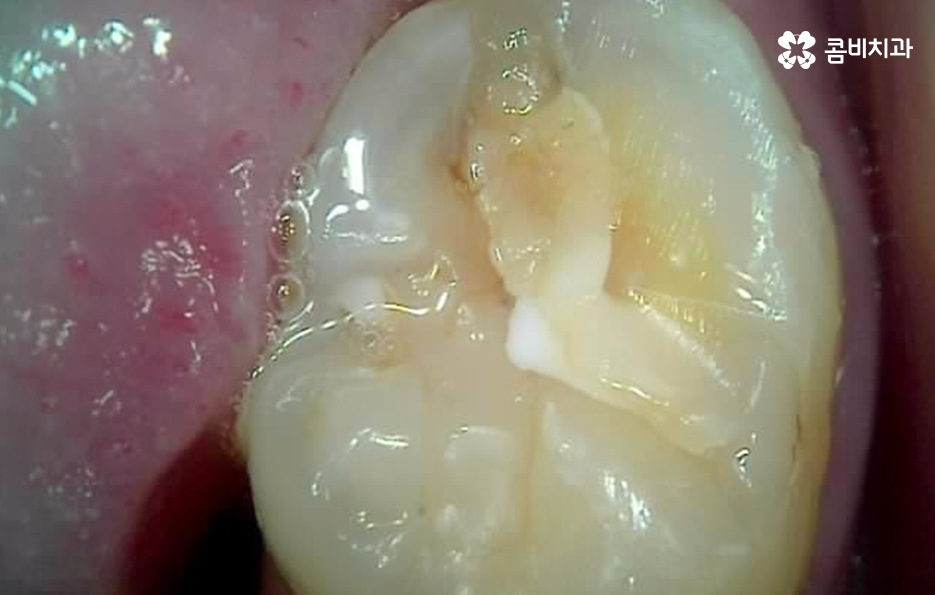

치과 치료 후 2차충치가 발생되는 이유에 대해서는 시간이 지날수록 보철물과 자연치아 사이에 틈이 발생할 수 있고 그 틈 사이로 세균이 침투하면서 발생되고 있는데요. 틈이 발생하는 원인에 대해서는 접착제가 서서히 녹을 수 있거나 레진과 같은 재료는 깨질 우려도 있고 보철물에 이상이 없더라도 자연치아 자체가 깨지거나 마모 되는 경우도 있어요

레진 2차충치 발생되는 원인은 오늘 전반적으로 설명드린 것처럼 치과 치료는 영구적인 치료가 아니고 보철물에는 수명과 교체 주기가 있으며 경우에 따라서는 레진의 깨짐, 탈락, 레진과 자연치아 사이에 틈이 발생하여 2차 충치가 발생하는 경우가 종종 있다는 점을 감안하셔서 불편함이 느껴진다면 바로 치료를 받는 것이 충치가 심해지는 것을 방지할 수 있어요

이미 보철 치료를 받았던 부위는 내부에서 2차충치가 발생된다면 눈으로는 상태를 확인하기 어렵기 때문에 자각증상을 통해서 치과에 갈지 고민하는 분들이 많이 있는데요.